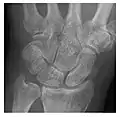

The general rule is to perform two orthogonal views, but more specific views should be added if there is any suspicion of fracture. Moreover, one should be aware of the commonly encountered lesions and their locations. In wrist trauma, for instance, the interpreter should pay close attention to the scaphoid and triquetrum, which are the two most commonly injured carpal bones. The mechanism of trauma may also be helpful to locate the potential fracture. A fall on an outstretched hand suggests scaphoid fracture. Although the classical presentation consists of a radiolucent line and cortical disruption, the radiographic signs will depend upon the time elapsed between the first clinical symptoms and the time of radiographic examination, the location of the fracture within the bone, and the ratio of cortical to cancellous bone. Particular attention should be paid when analysing the subchondral plate, which may be disrupted or deformed. In metaphyseal areas, delayed signs of fracture include a band of sclerosis perpendicular to the trabeculae, while diaphyseal fractures may present as periosteal thickening.[1]

Digital radiography known as tomosynthesis has been shown to be superior to conventional radiographs in the detection of occult fracture of the scaphoid. Tomosynthesis has the ability to demonstrate cortical, as well as moderately displaced trabecular fractures. Thus, the performance of tomosynthesis in detecting radiographically occult fractures is considered as comparable to CT.[1]

Triquetral fracture usually occurs on the dorsal aspect by impingement from the ulnar styloid or avulsion of strong ligamentous attachment. The dorsal avulsion fracture or "chip fracture" appears as a small bony fragment on the dorsal aspect of the triquetrum and is best detected on the lateral view(Figure 4). When radiography is negative in patients with high suspicion of a fracture, both MRI and MDCT will be of value. However, it has been shown that MRI is superior for detecting trabecular fractures in carpal bones.

a

b

Figure 4: Dorsal triquetral fracture of the left wrist in a 30-year-old man after a trauma. (a) Anteroposterior radiograph shows a normal appearance. (b) Lateral radiograph of the same wrist demonstrates a chip fracture off the dorsal aspect of the triquetrum (arrow).[1]